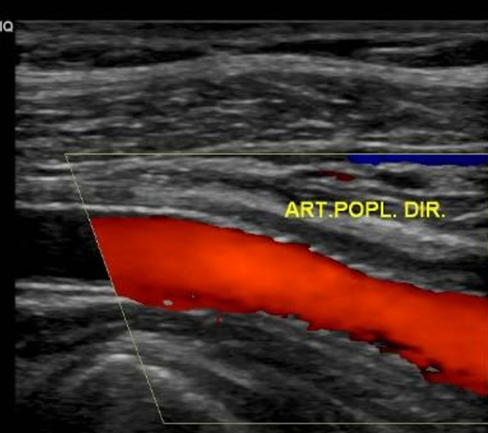

The patient was scheduled to undergo endovascular treatment of the popliteal artery aneurysm. Under general anesthesia, a right common femoral artery was antegrade punctured guided with a duplex ultrasound to perform the whole intervention percutaneously with a 6F 11cm sheat. After the puncture, the Perclose Proglideâ was inserted, in order to preload and guarantee the sealing of the puncture. Then, a 0,035”260cm Terumo â was used to perform the crossing over the distal arteries. The patient was heparinized with 5000UI intravenous in bolus. We performed a right limb arteriography to confirm the popliteal artery aneurysm (Figure 2). The popliteal artery was properly catheterized and we changed the guidewire for an Amplatz 0,035”260cm, in order to place a 11cm 11F sheat. After proper evaluation, two a covered self-expandable 8x100 and 10x75 Merit Wrapsodyâ were placed under roadmap into the distal popliteal artery and proximal femoral artery respectively, and post dilatated with a 8x100 and 10x100 catheter balloon Oceanus figures 3 and 4. There were no endoleaks, and the popliteal artery patency was identified. All the materials were removed, and we completed the final step of the perclose Proglideâ puncture closing. The patient was transferred to the nursery room, being discharged from the hospital two days after the surgery with no complications, femoral, popliteal and podal pulses present bilaterally, taking Rivaroxaban 20mg / day and Clopidogrel 75mg/day. After 1 month the patient was evaluated, presenting no further symptoms, no palpable mass in the right popliteal artery, and was submitted to a Duplex Ultrasound (Figure 5), that showed deep popliteal artery patency, stent patency, reduction of the aneurysm sac and no endoleaks. Furthermore, after one year follow-up, the patient remained asymptomatic, with Duplex Ultrasound showing popliteal artery with stent patency and no endoleaks. (Figure 6).

Figure 5: Duplex Ultrasound showing popliteal artery patency, stent patency and no endoleaks at 1 month.

Figure 6: Duplex Ultrasound showing popliteal artery patency, stent patency and no endoleaks at 1 year.